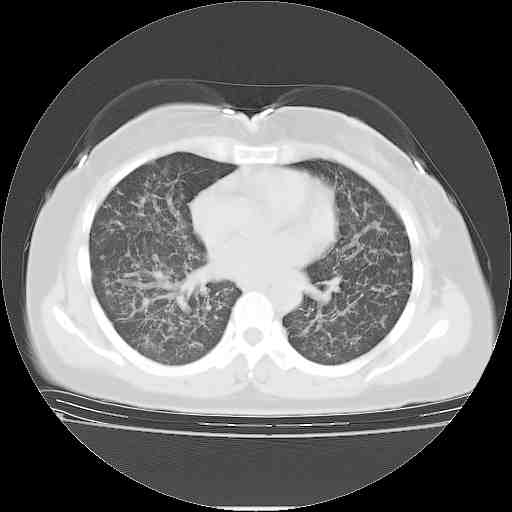

下面是今天刚刚做的,在上海治疗,吃了家属也说不清的一种药,一个月1万左右,

考虑  腺癌肺内转移,治疗较前病灶缩小、减少

支持肺癌并肺内淋巴管炎,  原发灶小了,但转移较前片明显了.

支气管血管束粗而乱,考虑肺癌肺内淋巴管转移,右侧乳房第一二层软组织成份较左侧多,不会有问题吧?

支持右肺下叶周围型肺癌并肺内淋巴管炎,  原发灶小了,但转移较前片明显了.。

标准的细支气管肺泡癌呀!治疗后病情有所控制,也没治愈的迹象!

标准的癌性淋巴管炎!!距大去之日不远已.